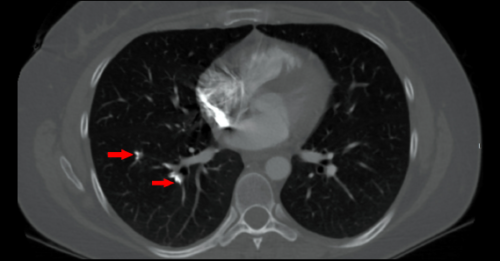

The Case A 36-year-old woman presented to the emergency department for generalized weakness. The patient stated that…